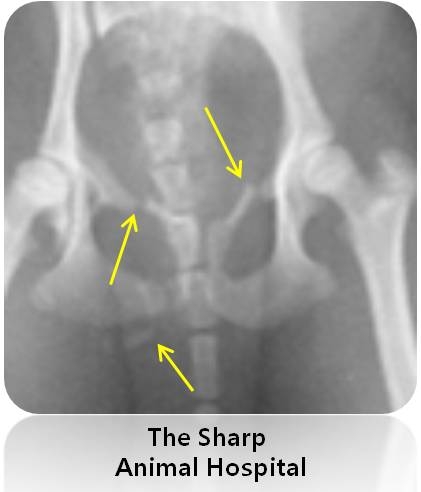

그런데 정작 문제는 골반골에 있었습니다.

골반골에 골절이 있었어요..

조금 확대 해서 보면 뿌러지 뼈 조각들이 나뉘어져 있는 것을 확인 하실 수 있습니다. ( 노란색 화살표 )

일단 부러진 골반골의 부위가 중요한 부위가 아니고 걸음걸이 치명적인 곳이 아니기 때문에

수술적 방법을 사용하지 않고 일반 깁스를 통하여 유지 하여 보기로 하였습니다.